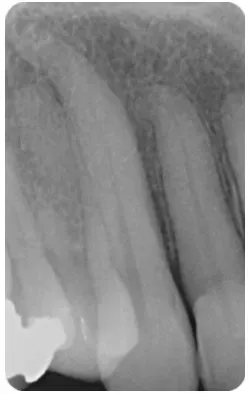

Chụp X-quang: Chóp hẹp được ước tính ngắn hơn từ 0.5 đến 1mm so với chóp x-quang. Tuy nhiên, vị trí và hình dạng của chóp hẹp có thể thay đổi, làm cho việc xác định chính xác bằng x-quang trở nên khó khăn.

Hai chiều: chụp X-quang là hình ảnh hai chiều và cung cấp góc nhìn hạn chế, đặc biệt là ở mặt phẳng má-lưỡi (Hình 4)